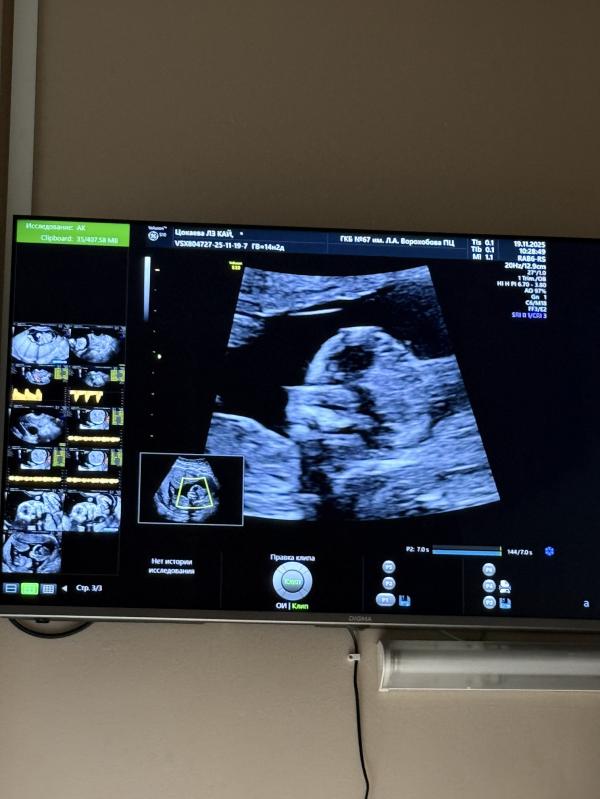

Была сегодня на скрининге 1, по факту втором 😀. Сначала пришла слишком рано ( в 11 недель ровно), а сегодня прыгнула в последний вагон ( ровно на 14 неделе) 😀

Сказали, что все хорошо, ноги руки увидели 😁 На узи крутился вертелся, нормально не давался 😁

На скрининг хожу в жк ГКБ 67 на Саляма Адиля. Здесь же буду рожать в мае. Очень большое сдание,новое, приятно находиться.